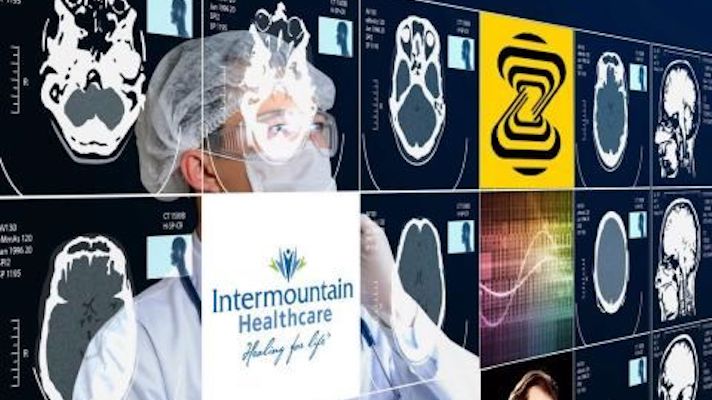

Several top medical societies have pledged a long-term partnership with the Human Diagnosis Project which uses machine learning algorithms to help providers find specialty treatment for their patients and could aid in care for 30 million Americans.